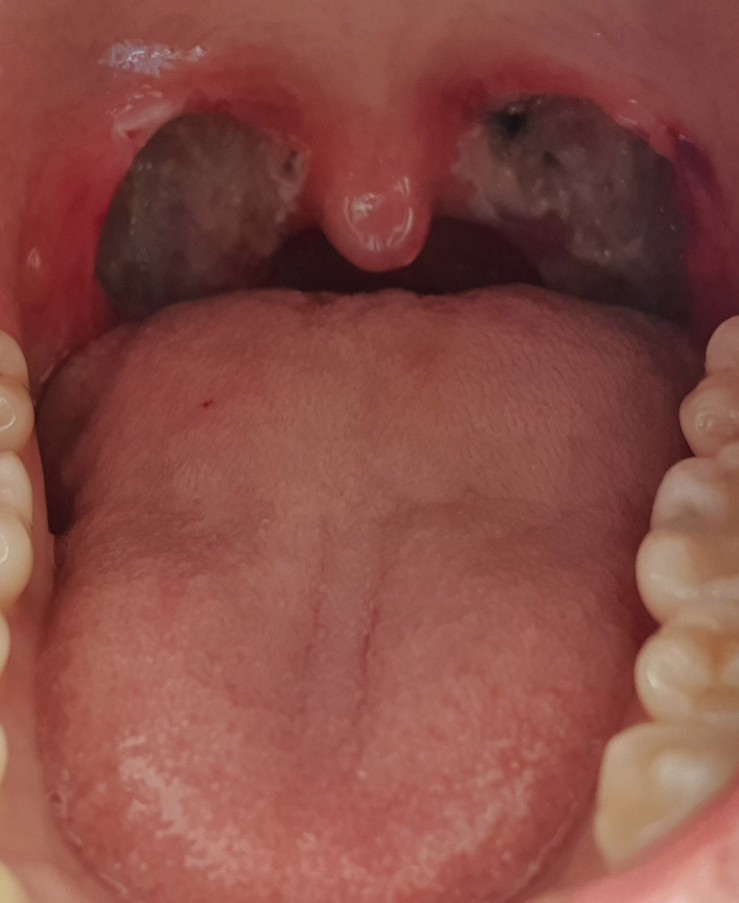

이것은 수술 전 내 편도선 자식의 사진으로 크기는 그리 크지 않았지만, 여느 편도보다는 비대해진 것이었다.

아주 깨끗이 제거했어ㅜㅜ 감사합니다!!! 하지만 보이는 검은 점? 빨간 상처?가 조금 불안해출혈은 안돼! 절대 지켜줘!!!!